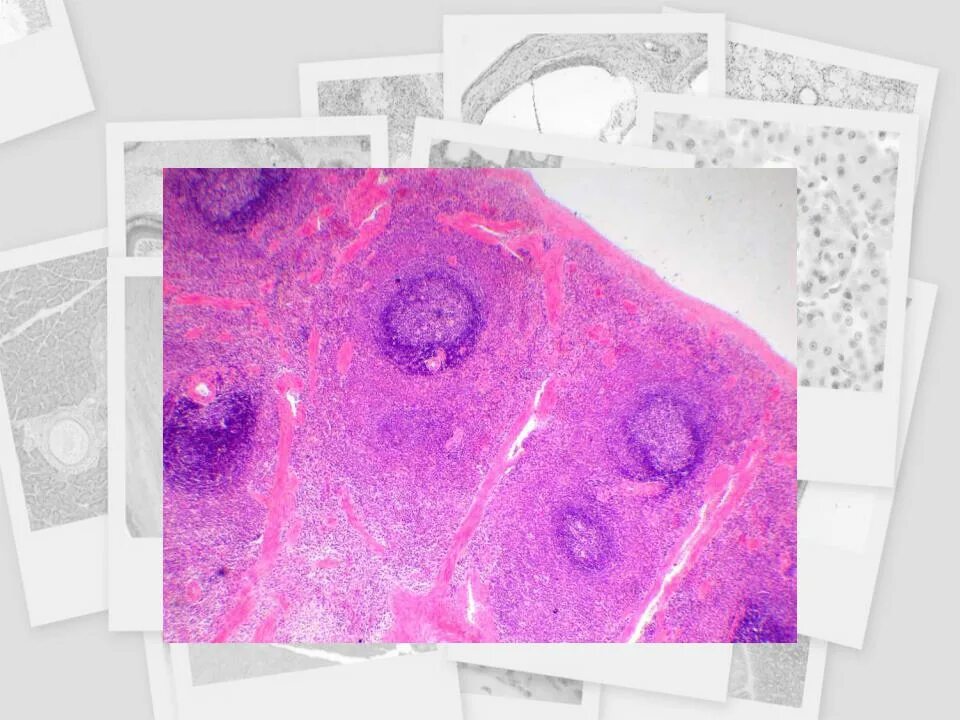

Селезенка препарат гистология